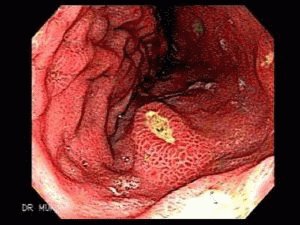

Виразка шлунку